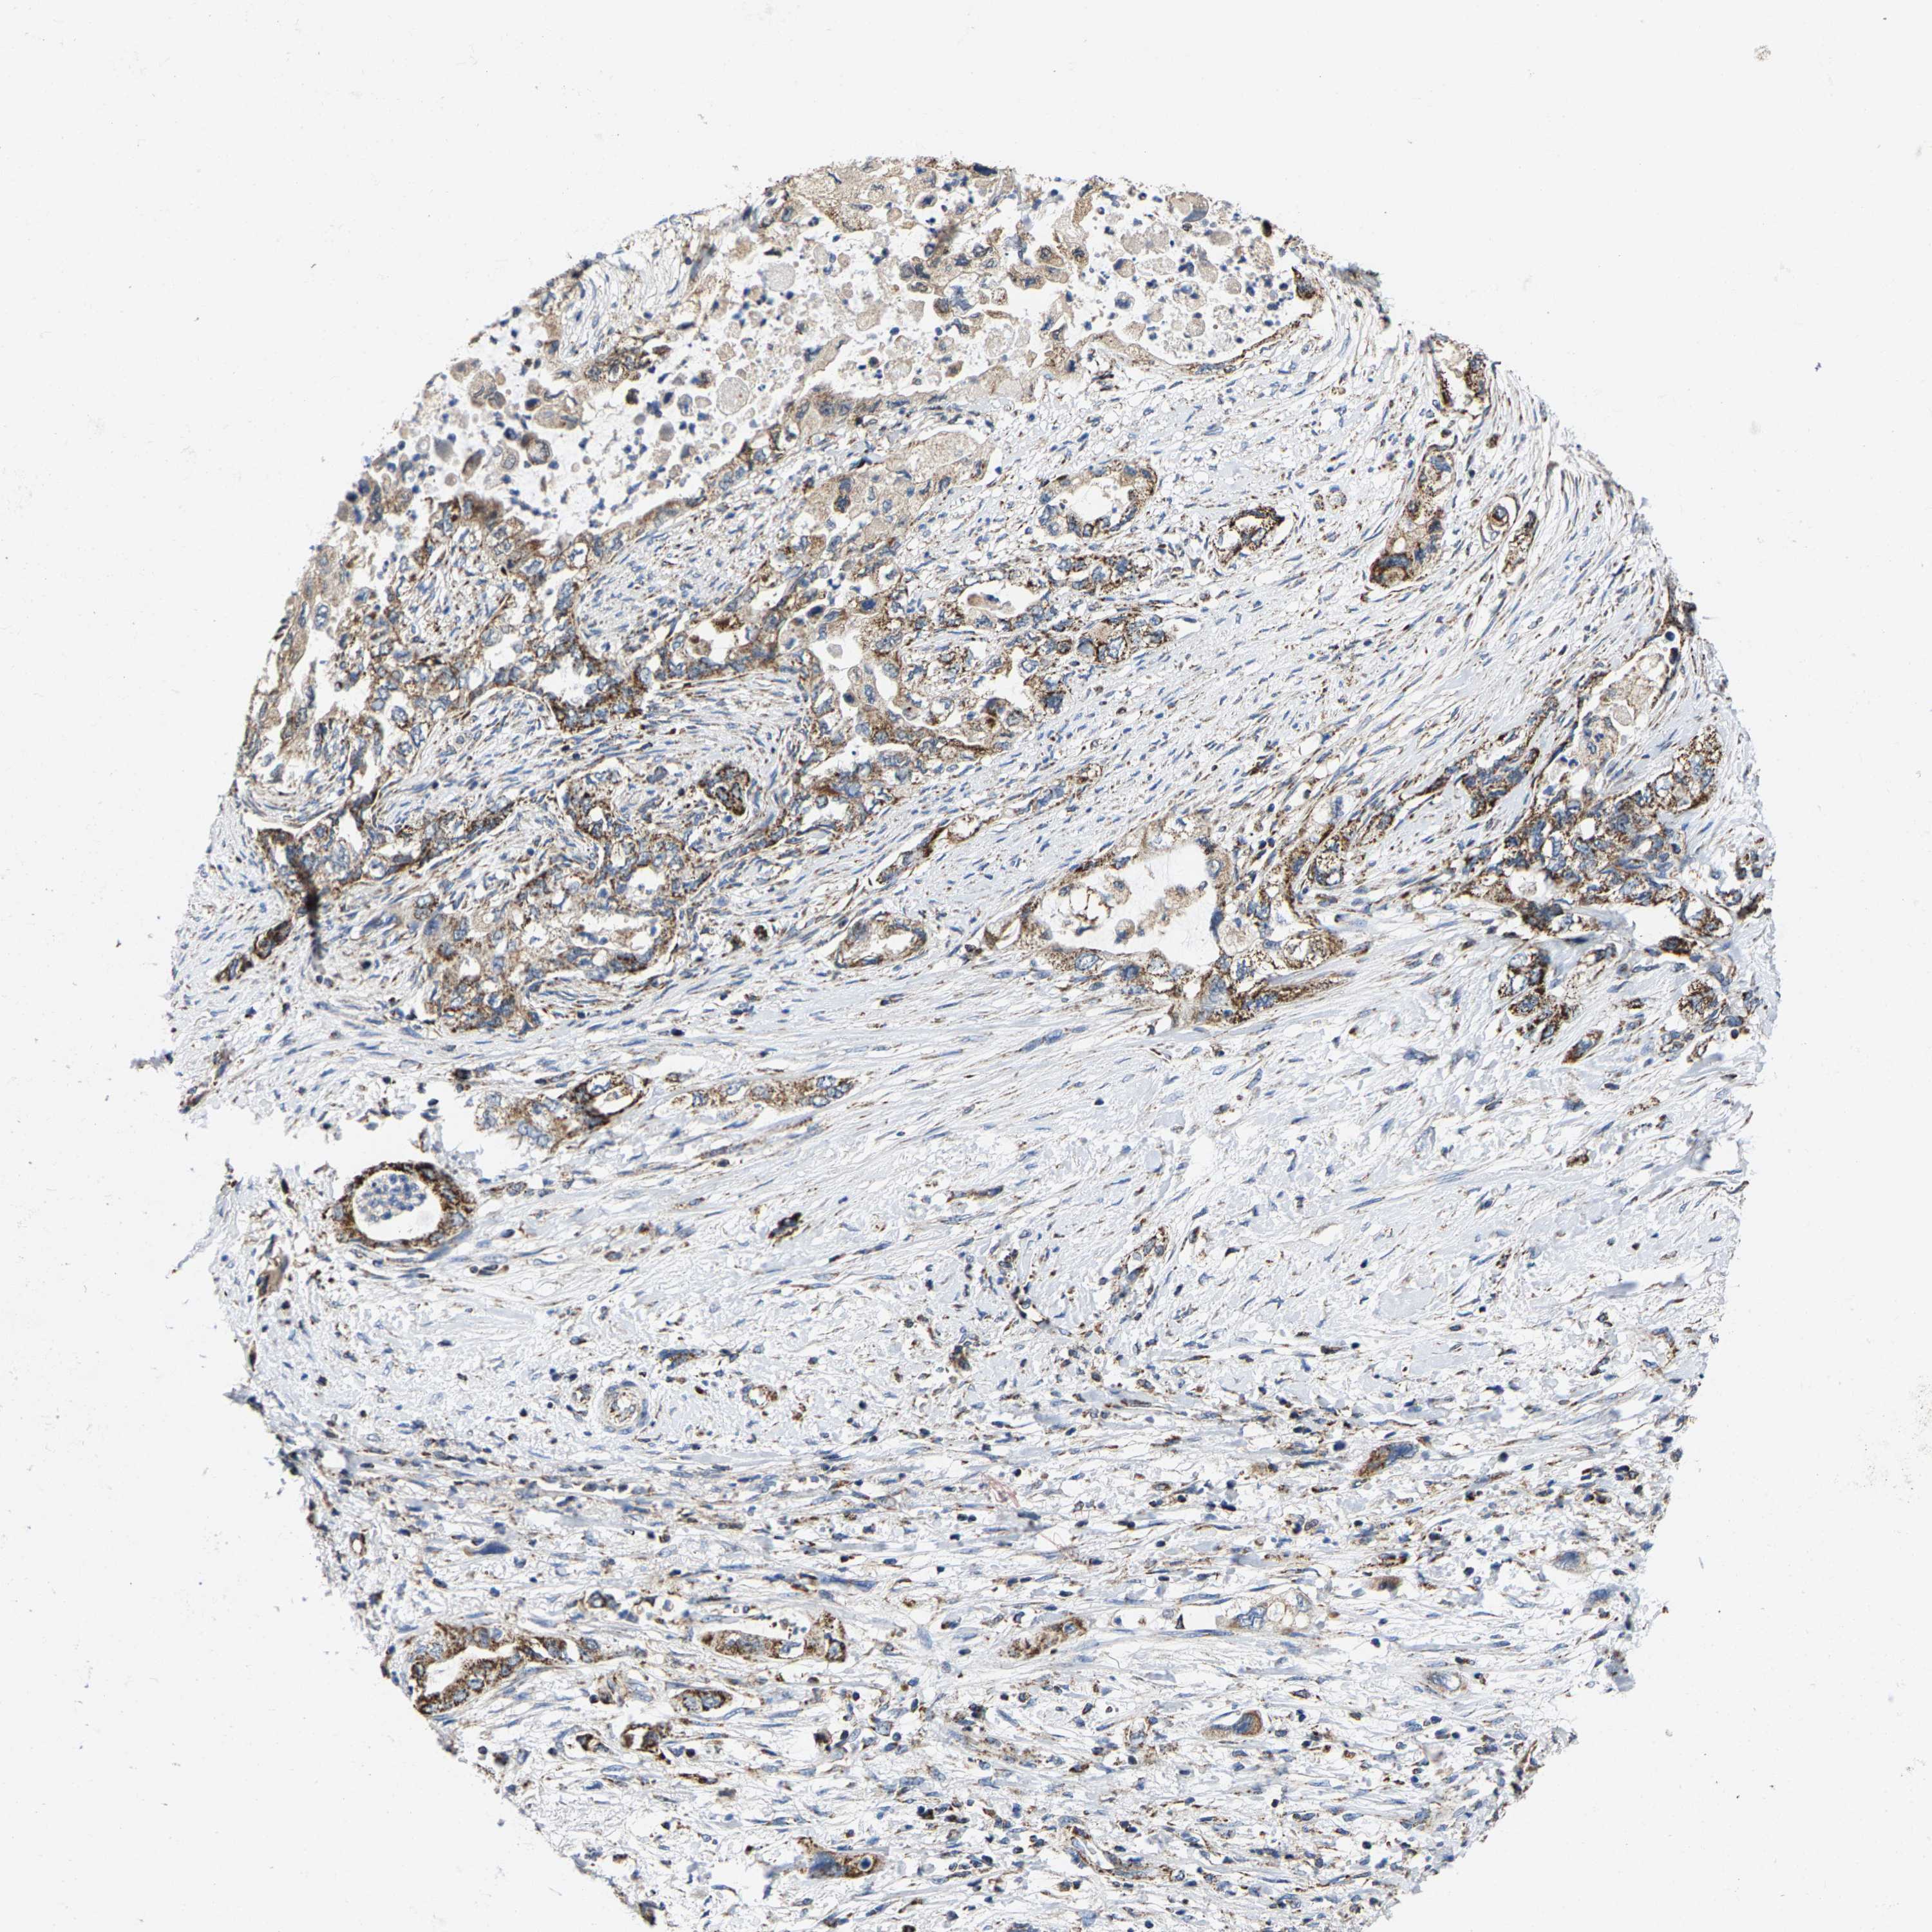

PANCREATIC CANCER - Protein expressioni

A mouse-over function shows sample information and annotation data. Click on an image to view it in a full screen mode. Samples can be filtered based on level of antibody staining by selecting one or several of the following categories: high, medium, low and not detected. The assay and annotation is described here.

Note that samples used for immunohistochemistry by the Human Protein Atlas do not correspond to samples in the TCGA dataset.

Antibody stainingi

Antibody staining in the annotated cell types in the current human tissue is reported as not detected, low, medium, or high, based on conventional immunohistochemistry profiling in selected tissues. This score is based on the combination of the staining intensity and fraction of stained cells.

Each image is clickable and will lead to virtual microscopy that enables deeper exploration of all samples and also displays staining intensity scores, fraction scores and subcellular localization as well as patient and tissue information for each sample.

Antibody HPA020543

Antibody HPA020549

Staining

High

Medium

Low

Not detected

Intensity

Strong

Moderate

Weak

Negative

Quantity

>75%

75%-25%

<25%

None

Location

Nuclear

Cytoplasmic/membranous

Cytoplasmic/membranous,nuclear

Adenocarcinoma, NOS